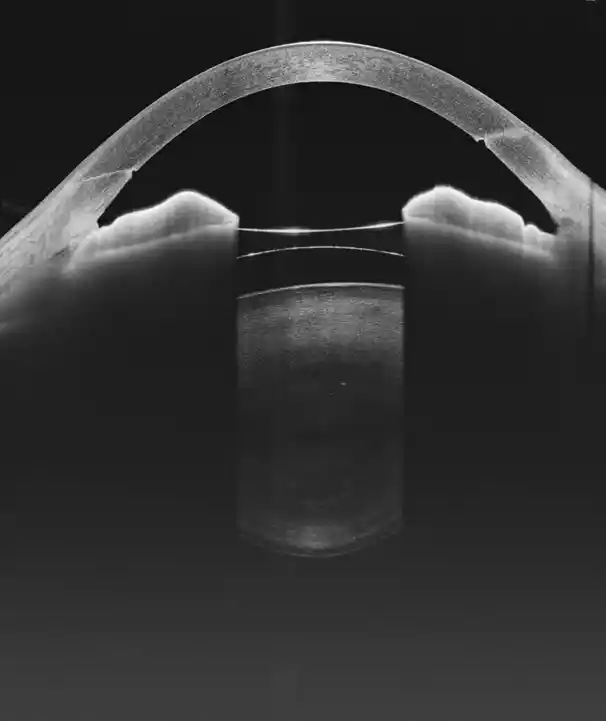

Głęboka penetracja

Urządzenie zapewnia większą głębokość skanu w tylnym odcinku (12 mm) i przednim odcinku (15 mm), co jest szczególnie korzystne w obrazowaniu ciała szklistego, naczyniówki oraz struktur przedniego odcinka

Optymalny balans

Stanowi idealny wybór do kompleksowego zastosowania OCT w jednym urządzeniu, oferując pełnozakresowe obrazowanie przedniego i tylnego segmentu oka

Analiza Segmentu Przedniego (AS)

Pomiary ilościowe, parametry panoramiczne, mapa grubości rogówki, głębokość komory przedniej i kąt przesączania